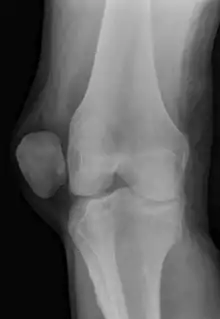

![]() | |

| X-ray showing a patellar dislocation, with the patella out to the side. | |